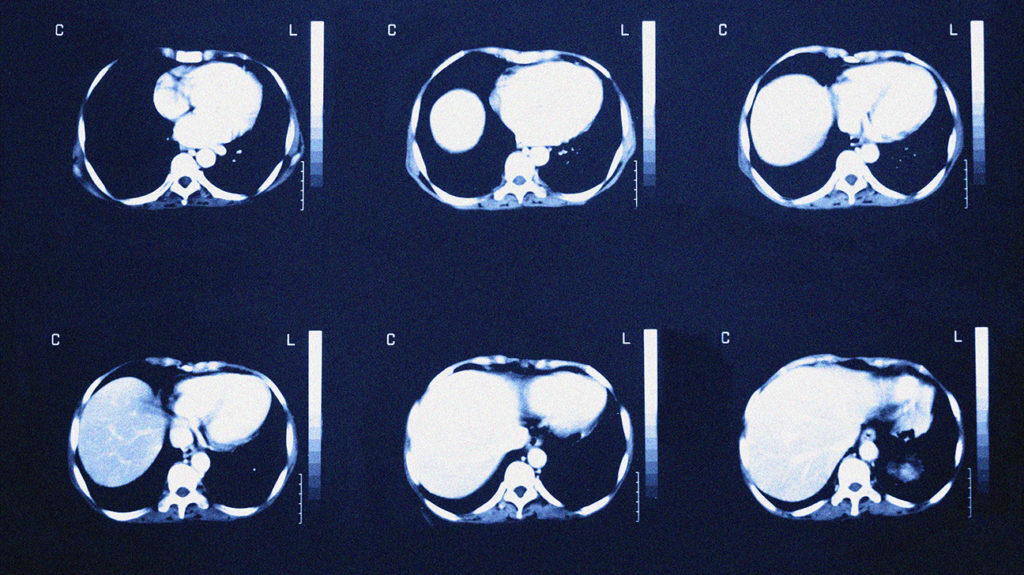

Три неочевидных признака нарушения работы селезёнки

В китайской медицине считается, что в нашем организме может накапливаться "влага», которая является причиной некоторых заболеваний. Её избыток можно определить по трём симптомам. Все они связаны с работой селезёнки. photorealm.ru »